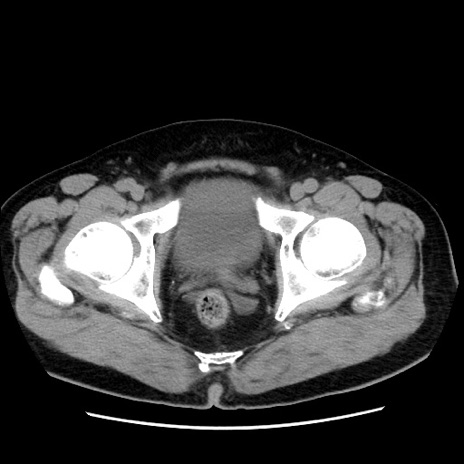

症例16(横断像)

【症例】 70歳代男性

【主訴】 腹痛、嘔吐

【現病歴】 約1ヶ月前より間欠的に腹痛と嘔吐あり、当院消化器内科を受診したところCTで多発する肝臓のLDAを指摘され、精査中であった。以降は消化器症状は安定していたが、2日前より嘔気と腹痛があり、同日より排便・排ガスが消失した。改善認めず、 本日、救急外来を受診した。

【身体所見】意識清明・会話良好、BT 36.3℃、BP 127/80mmHg、 P 80bpm、腹部:膨満あり、平坦・軟、上腹部正中および下腹部正中に圧痛あり、反跳痛なし、筋性防御なし。

【データ】WBC 7200、CRP 0.77